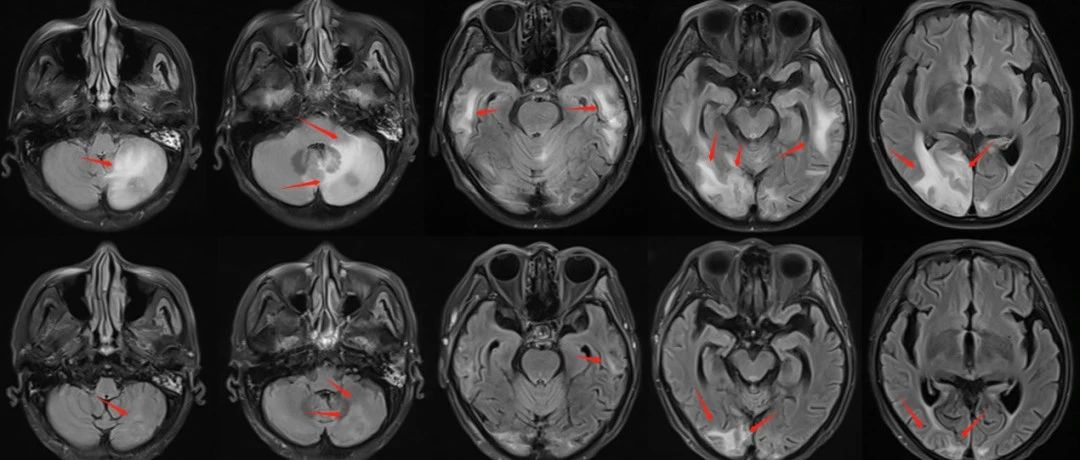

經(jīng)過3周(15次)次放療,患者病情得到良好控制。復(fù)查磁共振檢查可見腦內(nèi)病灶明顯縮小,大部分消失;瘤周水腫基本消散。證明腫瘤病灶活性喪失,得到徹底控制;也說明治療劑量方案得當(dāng),患者沒有發(fā)生放射性腦損傷。單次治療不足3分鐘,過程順利,患者無明顯不良反應(yīng)發(fā)生。療后復(fù)查病灶完全控制,患者安返內(nèi)蒙古老家。

圖注:治療3周后復(fù)查磁共振顯示,T1增強(qiáng)掃描可見顱內(nèi)強(qiáng)化轉(zhuǎn)移病灶較前明顯縮退,部分消失。并且,放療后病灶仍將進(jìn)一步消退。

圖注:治療結(jié)束時(shí)復(fù)查磁共振顯示,T2FLARE像可見轉(zhuǎn)移瘤周水腫基本消退。說明腫瘤病灶活性喪失,得到徹底控制;也說明沒有放射性腦損傷發(fā)生。